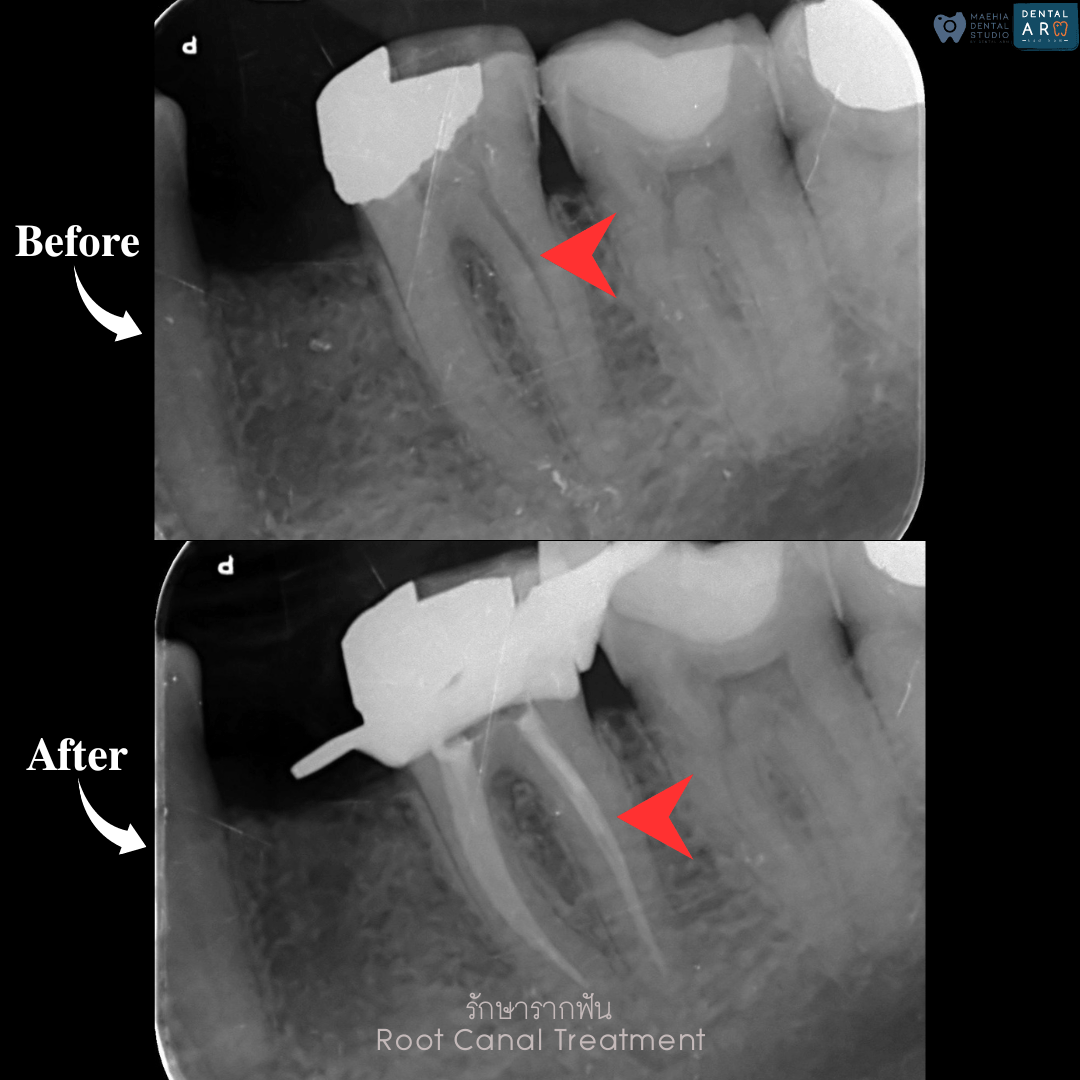

รักษารากฟัน

คือ การรักษาฟันที่เกิดการอักเสบและติดเชื้อภายในโพรงประสาทฟัน และเนื้อเยื่อรอบปลายรากฟัน อันมีสาเหตุมาการอักเสบและติดเชื้อภายในรากฟัน โดยทันตแพทย์จะทำการทำความสะอาดและใส่ยาในคลองรากฟัน และทำการอุดรากฟันเป็นขั้นตอนสุดท้าย การรักษารากฟันจะช่วยเก็บรักษาฟันให้สามารถคงอยู่ในช่องปากต่อได้ โดยไม่ต้องถอนฟันและไม่ต้องใส่ฟันทดแทน